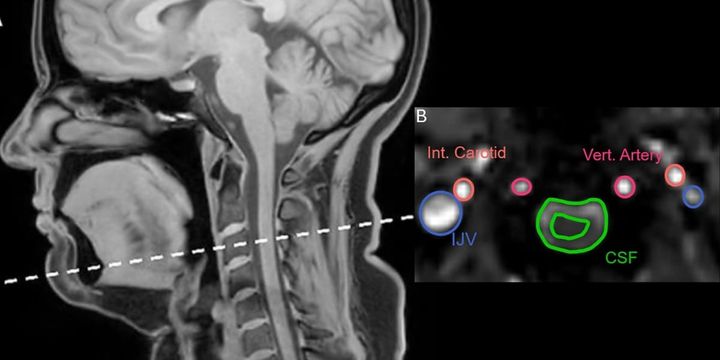

答えを得るため研究チームはまず、健康な大人を磁気共鳴画像装置に入ってもらい、「ふつうの呼吸」「口を大きく開けた深呼吸」「あくび動画を見て自然に出たあくび」「あくびをこらえたとき」の四つの動きをしてもらいました。

そのあいだに首の上の方、首の骨でいうと三番目あたりで、脳脊髄液の流れと内頸静脈を流れる血液の流れが、どの向きにどれくらいの速さで動くのかを、別々に連続的に記録しました。

ところが、流れの「向き」までくわしく調べると、深呼吸とあくびでは、はっきりした違いが見つかりました。

まず深呼吸で大きく息を吸ったときには、脳脊髄液は頭の方へ向かって流れ、血液は首から胸の方へ向かって流れ出していくパターンが多く見られました。

簡単にいうと、深呼吸では「水は上へ、血は下へ」という結果です。

これに対して、多くのあくびでは、口を大きく開けてぐっと息を吸い込む瞬間に、脳脊髄液と静脈の血液がどちらも頭から首へ、つまり下のほうへ流れるというパターンがみられました。

頭の中の水路からも、血の通り道からも、中身がまとめて首の方に引っぱり出されるような動きです。

深呼吸が「水は上へ、血は下へ」ならば、あくびは「水は下へ、血も下へ」という傾向が見えてきたのです。